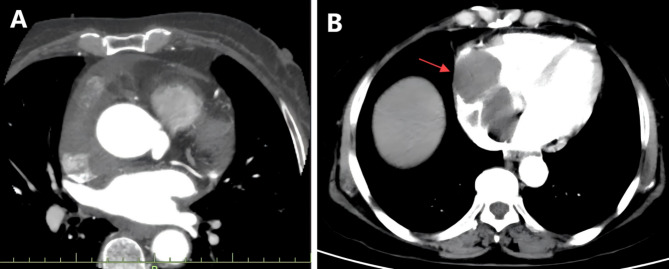

Case presentation: We report the case of a 68-year-old woman presenting with palpitations, dizziness, and obstructive cardiac symptoms. Diagnostic imaging revealed a large mass in the right atrium near the superior vena cava. A novel "zongzi"-shaped endoscopic gauze folding technique was employed to facilitate complete tumor resection while preserving cardiac structure. Pathology confirmed double expressor DLBCL with BCL2 and MYC co-expression, indicating a high-risk profile. The patient's postoperative course was uneventful, and she was discharged in stable condition. However, follow-up imaging at six months revealed local disease progression.